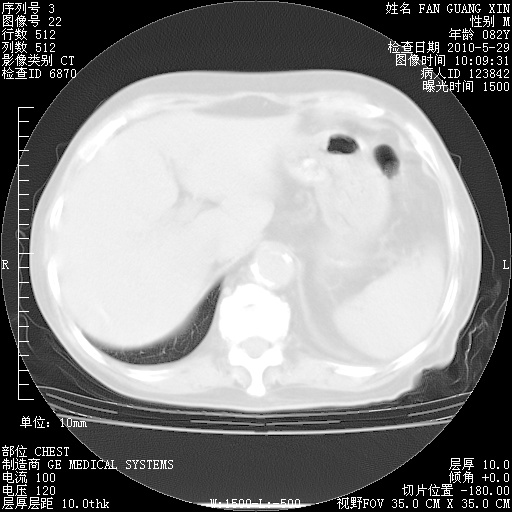

发表于 2010-5-19 19:23

还需要哪些辅助检查?我们医院排除真菌感染没有任何检验方法,胸片好像能够排除肺部真菌感染。

补充:ENA化验全部阴性。免疫五项(IgG、IgA、IgM、C3、C4)只有C4略高。